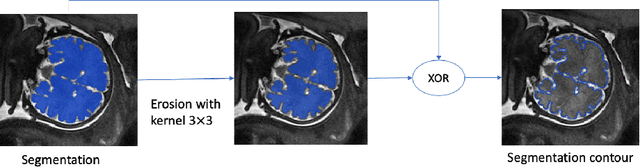

Abstract:Volumetric measurements of fetal structures in MRI are time consuming and error prone and therefore require automatic segmentation. Placenta segmentation and accurate fetal brain segmentation for gyrification assessment are particularly challenging because of the placenta fuzzy boundaries and the fetal brain cortex complex foldings. In this paper, we study the use of the Contour Dice loss for both problems and compare it to other boundary losses and to the combined Dice and Cross-Entropy loss. The loss is computed efficiently for each slice via erosion, dilation and XOR operators. We describe a new formulation of the loss akin to the Contour Dice metric. The combination of the Dice loss and the Contour Dice yielded the best performance for placenta segmentation. For fetal brain segmentation, the best performing loss was the combined Dice with Cross-Entropy loss followed by the Dice with Contour Dice loss, which performed better than other boundary losses.